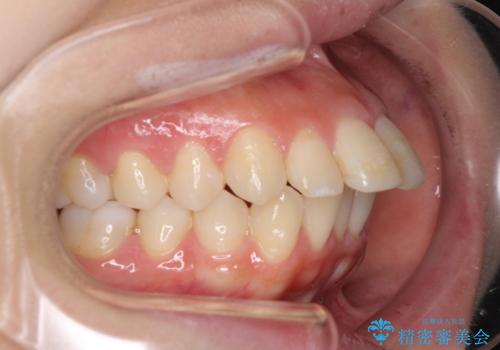

突出した口元が気になる ハーフリンガル装置による抜歯矯正

- 口元の突出感を気にして来院された患者様です。

通常では上下左右の第一小臼歯4本を抜歯しますが、下顎が左側にシフトしていたため、下顎左側のみ第二小臼歯を抜歯し、正中を合わせながら口元を下げる治療計画としました。

ハーフリンガルは、通常では表側のワイヤー矯正よりも治療期間がかかります。特に今回のように下顎左側をイレギュラーの第二小臼歯抜歯としたため、さらに時間がかかることが予想されました。

実際に治療をおこなってみると、2年を切る短期間で治療を終えることができました。